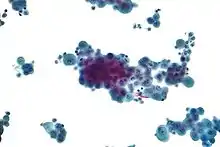

Micrograph of a pleural fluid cytopathology specimen showing malignant mesothelioma, one cause of a pleural effusion.

- If cancer is suspected, the pleural fluid is sent for cytology. If cytology is negative, and cancer is still suspected, either a thoracoscopy, or needle biopsy[5] of the pleura may be performed.

- Cytopathology to identify cancer cells, but may also identify some infective organisms